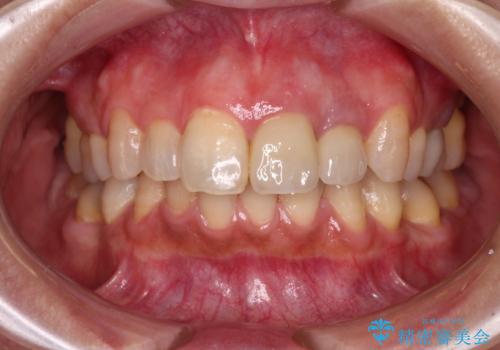

仮歯を装着した時点で、口元が気にならなくなったので、患者様が感じていた違和感の原因は変色した前から2番目の歯であったと思われます。

形態や色彩が左右対称となるように仕上がり、患者様には大変満足していただきました。